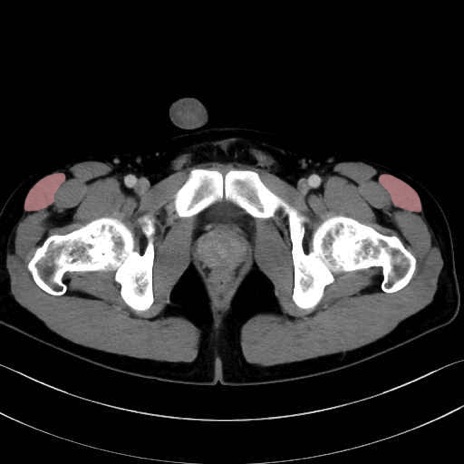

大腿筋膜張筋 (Tensor fasciae latae)